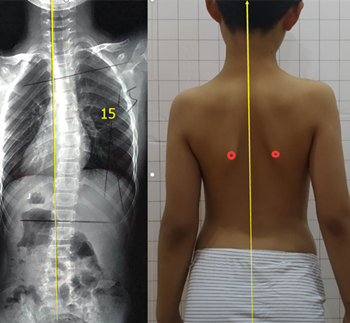

發(fā)現(xiàn)脊柱側(cè)彎要及時(shí)干預(yù)

青少年脊柱側(cè)彎一旦被家長(zhǎng)發(fā)現(xiàn),應(yīng)積極治療,阻止側(cè)彎進(jìn)一步加重但也有一些孩子,在發(fā)現(xiàn)脊柱側(cè)彎后,由于醫(yī)生判斷失誤,家長(zhǎng)不重視等等原因,沒有采取任何治療。發(fā)育期的孩子明顯增加較快,每個(gè)月基本增加1度。每年12度左右。

盡早展開學(xué)校脊柱側(cè)彎篩查,在30度以內(nèi)發(fā)現(xiàn),最后可以治療到低于20度。如果這樣,對(duì)孩子的影響幾乎可以忽略。